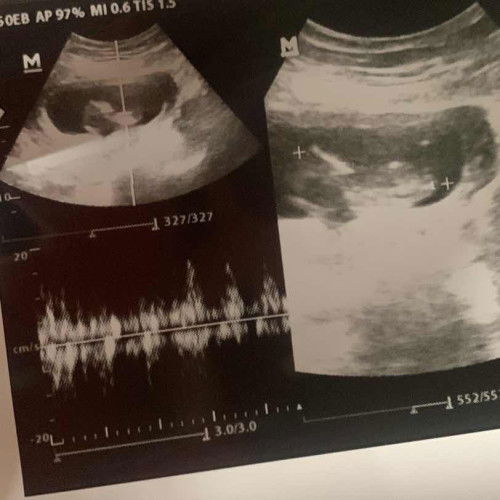

Hasil usg 11 weeks

Alhamdulillah sehat semua moms, bayi juga aktif. tangan sama kakinya juga udah nampak jelas semua hehe🥰🥰 sehat2 ya moms yang disini juga 🙏🏻 #firstTime_mom